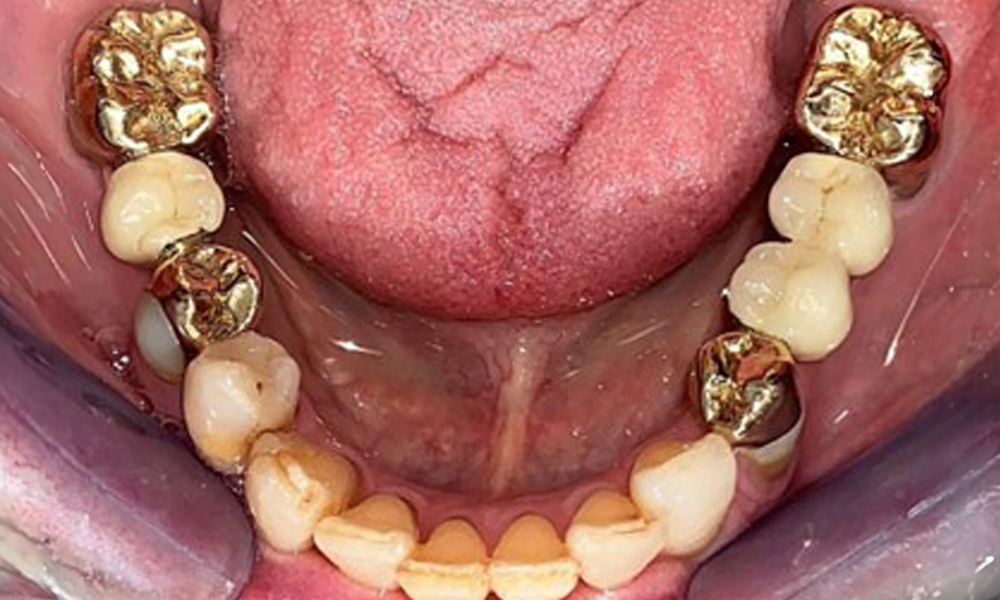

The dental findings are as follows: Combined removable implant and tooth-supported telescopic prostheses on implants 15, 13, 21, 23, 24, 25 and tooth 11 (Fig. 1, Fig. 2, Fig. 3). The patient was fitted with a fixed mandibular denture. Adequate bridges were present over 37 to 34 and 45 to 47 (Fig. 4), the crown margins were intact and there were no active caries. A composite filling with a marginal gap was present on tooth 43. There was mandibular gingival recession, exposing 1 to 3 mm of root surface. This also applies to 11.

Occlusal view of the mandible.

Fig. 4: Occlusal view of the mandible.